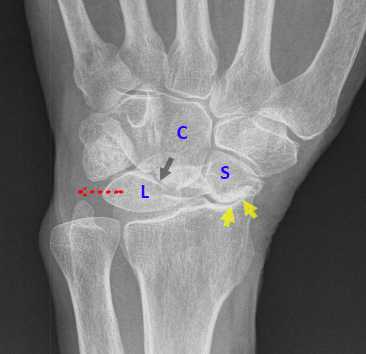

File: IMG_3079.jpg (214 KB, 908x657)

After 2+ years of back and forth with like 5 different doctors, I was finally able to convince one last month to send me for an MRI with contrast which show my wrist is completely fucked. There’s a lot wrong, but the biggest things are that I have a full thickness tear of my scapholunate (the surgeon literally said that it’s “gone”) and a partial tear in my TFCC. I need total reconstruction of the scapholunate and the jury is still out for how significant the tear in the TFCC is which will determine the surgical procedure they use for it. I know my wrist is never going to be the same, but has anyone else dealt with something like this before? I’d love to hear others’ experiences. Thanks!